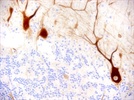

A variety of new products offer solutions to keep cells or tissues on a microscope slides.

read more